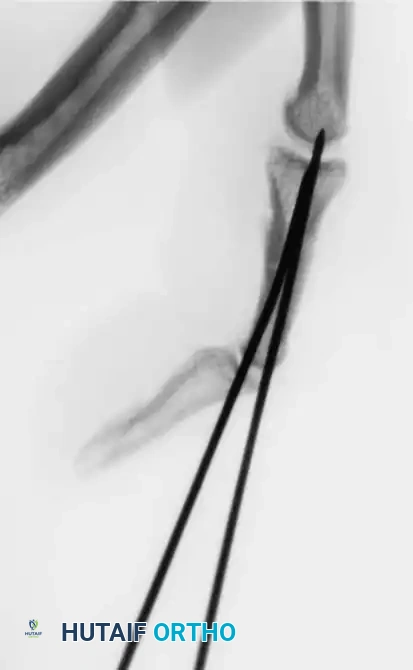

Percutaneous Techniques: Belsky-Eaton Pinning

Sometimes an unstable oblique fracture of a middle or proximal phalanx can be treated by closed reduction and percutaneous pinning. Belsky and Eaton described a highly effective technique for pinning multiple proximal phalangeal fractures without opening the fracture site.

Step-by-Step Technique:

* The fractured phalanx is held reduced with the MCP joint flexed to 90 degrees. This tightens the collateral ligaments, using them as a tension band to align the proximal fragment.

* A single K-wire is drilled from the dorsal aspect of the metacarpal head, passing across the MCP joint and straight down the medullary canal of the proximal phalanx to cross the fracture.

* Crucial Step: The wire must not cross the PIP joint.

* Leave the wire exposed proximally (bent outside the skin) to allow for easy removal in the clinic at 3 to 4 weeks.